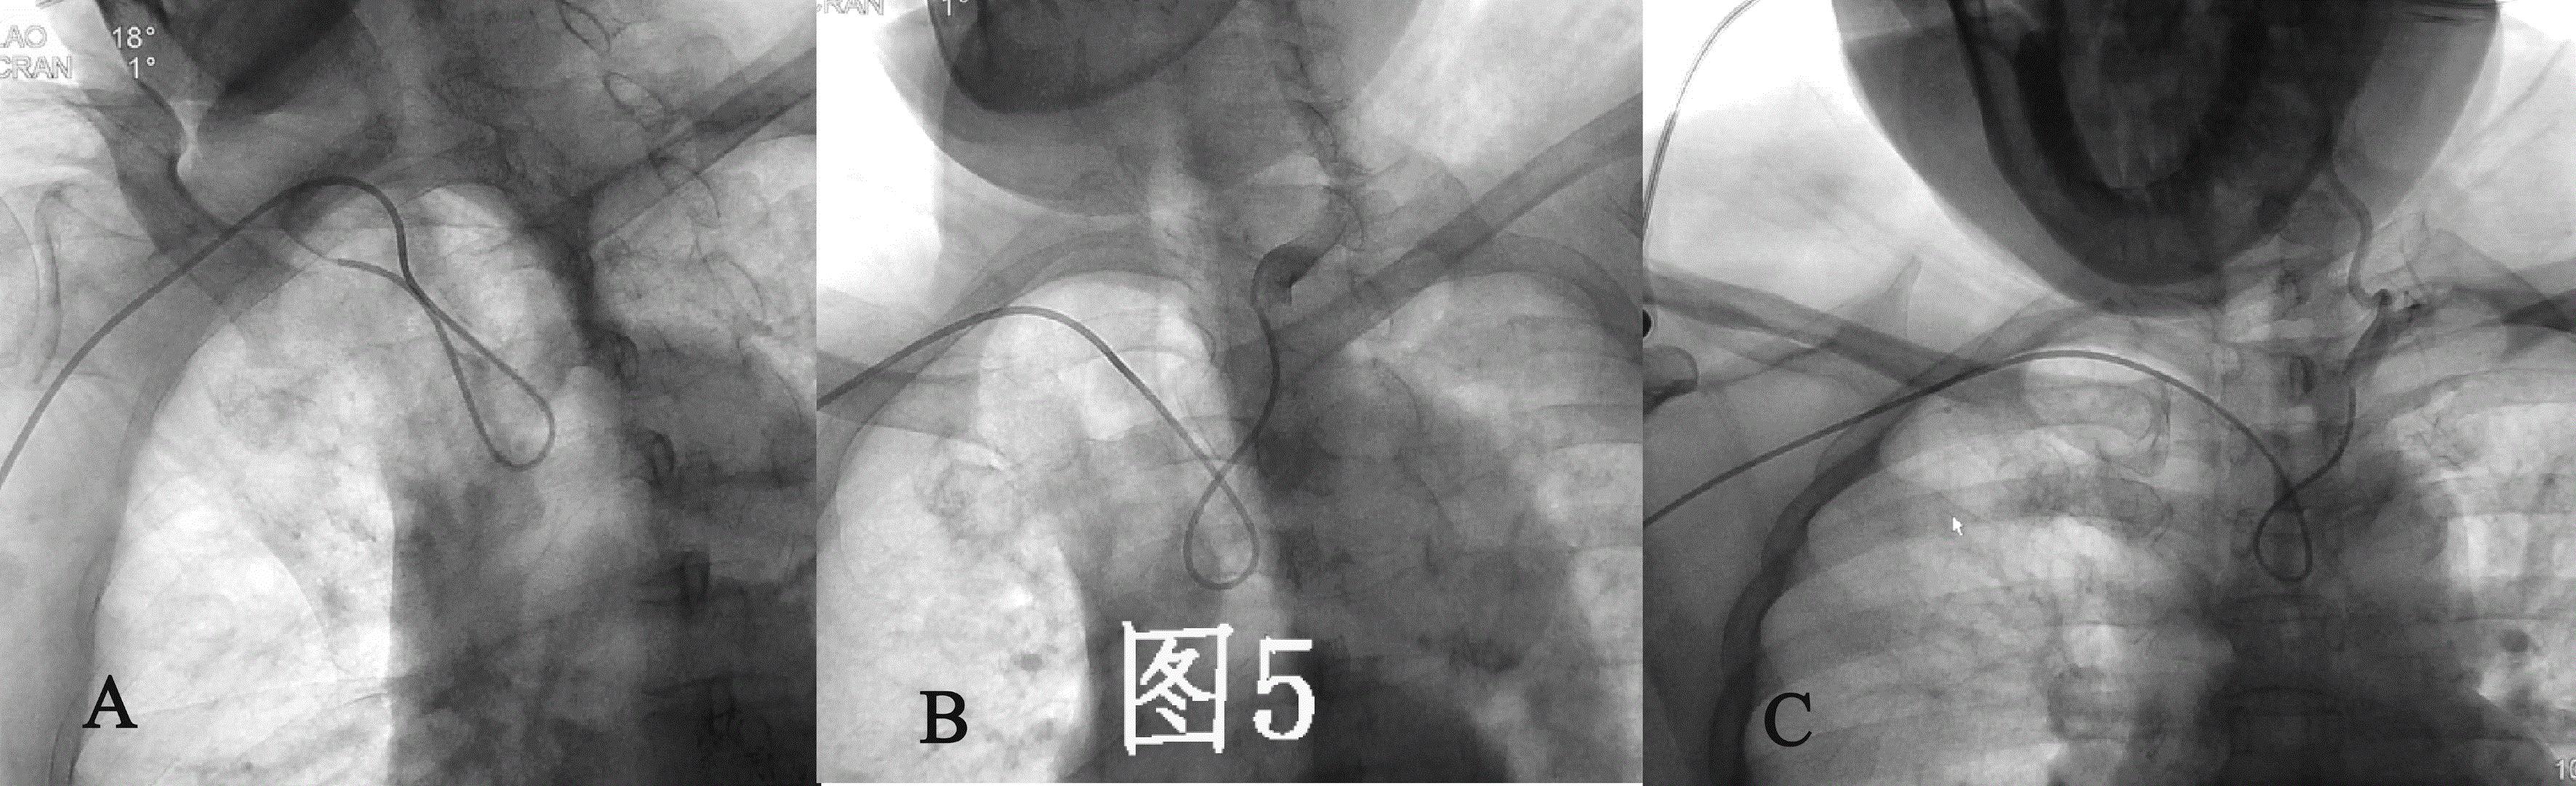

目前经桡动脉全脑血管造影通常选用的导管为西蒙造影导管,依据导管外形尺寸的大小分为三种型号,其中II-III型管均可被用于经桡动脉全脑血管造影(图4 A、B)。 西蒙造影导管的形状是按照经股动脉入路设计的,第一个弯在导管远端越过主动脉弓后可骑跨在主动脉弓上作为支点,而第二个弯曲则引导导管头端向上翘起,可选择性的进入无名动脉、左颈总动脉或左锁骨下动脉其中的任何一支血管(图3A)。 但是,在经桡动脉入路时,导管的第一弯曲无法骑跨在主动脉弓上,导管的第二弯曲引导的导管末端方向向下,这与脑主要血管的开口方向相反(图3B)。